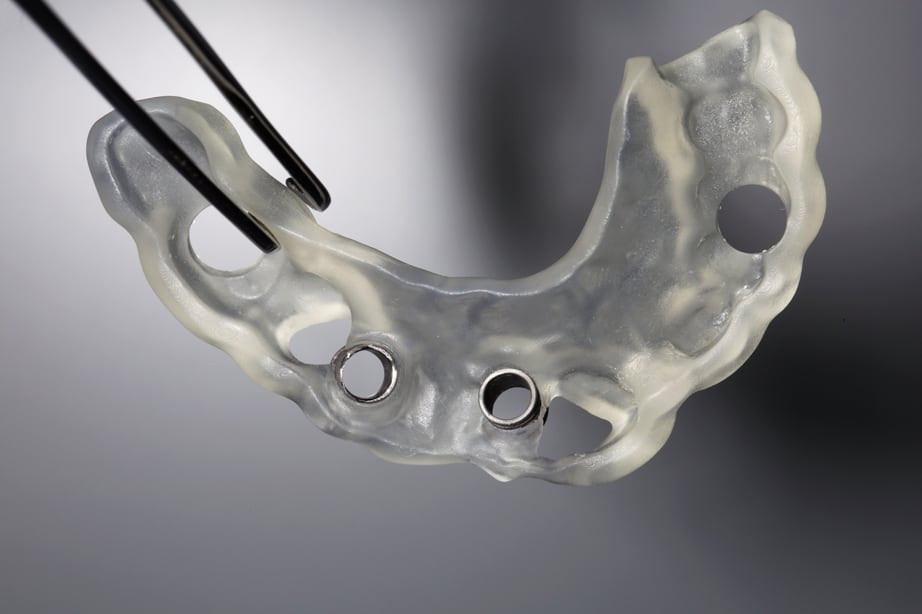

Auf Basis dieses vorgefertigten Datensatzes läßt sich das operative Vorgehen nun exakt am Computer planen und im Nachgang in eine sogenannte Bohrschablone, die mit einen 3 D Drucker hergestellt wird, in die reale Welt übersetzen.

Die hohe Präzision des chirurgischen Eingriffs mit Hilfe des computergestützen Planungsverfahrens verhindert außerdem Fehlstellungen von Implantaten und garantiert ein perfektes Ergebnis.